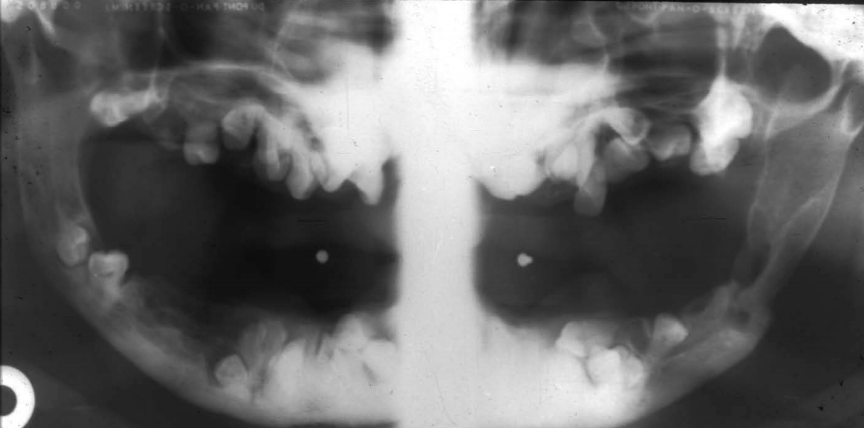

3 radiographic findings of cleidocranial dysplasia

A

• Prolonged retention of deciduous teeth

• Mulitple unerupted supernamary teeth resembling premolars

• Maxillary hypoplasia